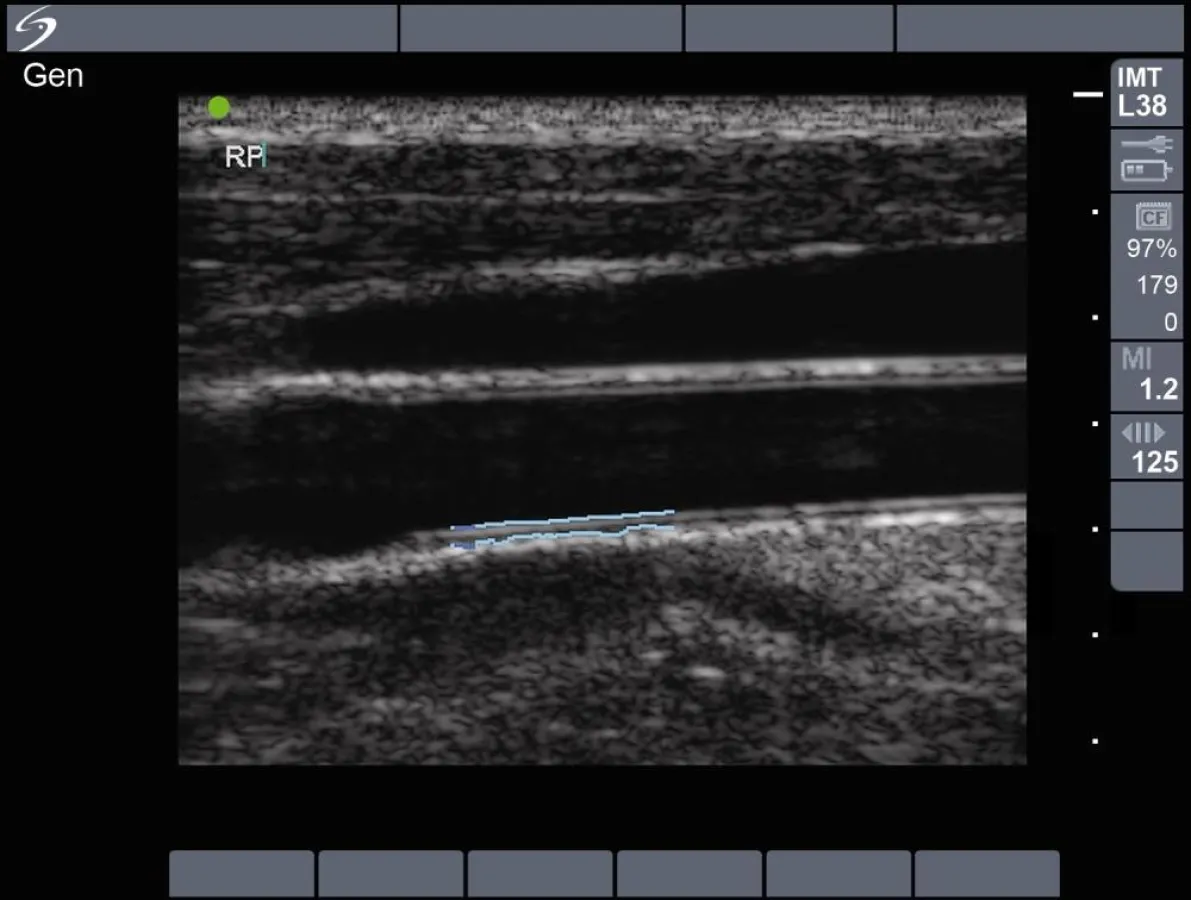

Im Rahmen der Studie untersuchte Dr. Postley 120 Patienten aus seiner Praxis per Ultraschall auf Ablagerungen in der Arteria carotis oder femoralis und erfasste ebenfalls die Intima-Media Thickness (IMT) der A. carotis. Unter den 50 teilnehmenden Frauen fand Dr. Postley keine Korrelation zwischen dem Framingham Score und der Verdickung der Gefäßinnenhaut der A. carotis, allgemein ein anerkanntes Indiz für kardiovaskuläre Erkrankungen. Darüber hinaus zeigten 50 Prozent der Frauen Plaques, während 72 Prozent dieser Gruppe laut Framingham nur ein geringes Herzinfarktrisiko hatten. Gerade bei Nichtvorhandensein anderer Risikofaktoren sind Plaques ein Hinweis auf einen drohenden Herzinfarkt oder Schlaganfall.

Alle Messungen der IMT der A. carotis wurden mit SonoSite TITAN®-Systemen durchgeführt, die mit der patentierten Software SonoCalc™ IMT mit Automated Edge Detection (automatische Intima-Wanderkennung) ausgestattet sind. Diese Ergebnisse können in Verbindung mit anderen medizinischen Daten genutzt werden, um den kardiovaskulären Gesundheitszustand eines Patienten einzuschätzen. Dr. Postley ist Mitglied des IMT Advisory Board von SonoSite, einer Gruppe von Allgemeinärzten, Kardiologen und Neurologen, die sich mit der Auswertung der IMT der A. carotis und den damit verbundenen Möglichkeiten für die ärztliche Untersuchung und die effektivere Erkennung und Behandlung von Risikopatienten beschäftigen.

In der vorliegenden Studie wurden 120 bisher unbehandelte Patienten aus einer an einer Universität angesiedelten Gemeinschaftspraxis zufällig ausgewählt. Mit Hilfe von Ultraschall wurden sie auf das Vorhandensein und die Art von Plaques an der Verzweigung der A. carotis und femoralis untersucht. Des Weiteren wurde die Dicke der IMT der A. carotis bestimmt. Die 50 Frauen und 70 Männer waren zwischen 34 und 74 Jahre alt. Der FRS verteilte sich bei den Männern folgendermaßen: 0-6: 31 %, 7-12: 39 %, 13-25: 30 % und bei den Frauen: 0-6: 72 % und 7-18: 28 %.

Die Korrelation des FRS zur durchschnittlichen IMT der A. carotis lag für alle Patienten bei r = 0,40 (p < 0,001) und die Korrelation des FRS zur maximalen IMT der A. carotis bei r = 0,40 (p < 0,001). Betrachtet man die Ergebnisse geschlechtsspezifisch, war die Korrelation des FRS mit der durchschnittlichen IMT der A. carotis (r = 0,49) und maximalen IMT der A. carotis (r = 0,47) bei den Männern sehr deutlich (p < 0,001), während es keine Korrelation für die durchschnittliche IMT der A. carotis (r = 0,04, p = 0,7) oder für die maximale IMT der A. carotis (r = 0,07, p = 0,6) bei den Frauen gab.